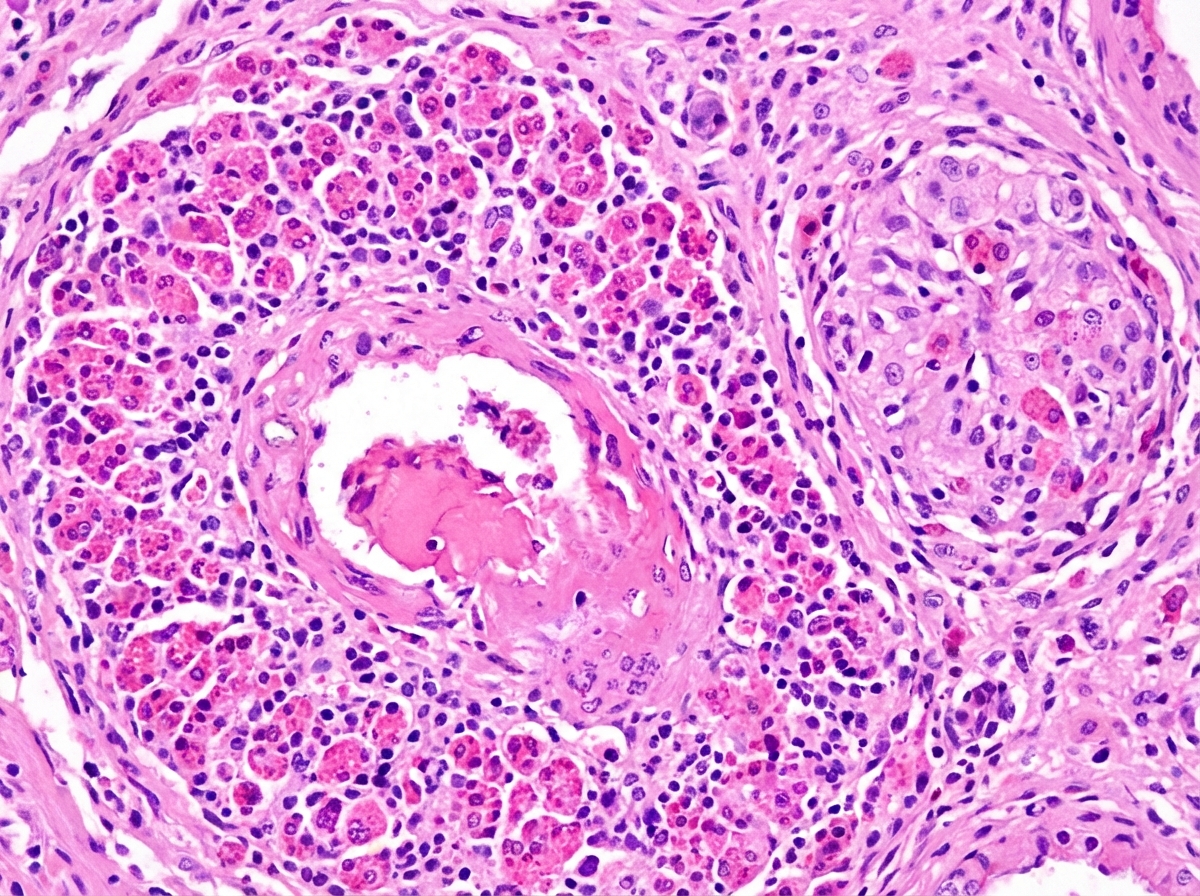

A 35-year-old patient presents with persistent allergic rhinitis, asthmatic episodes, and peripheral hypereosinophilia. Histological findings are shown below. What is your diagnosis?

Explanation: ***Churg-Strauss syndrome*** - The **clinical triad** of **allergic rhinitis**, **asthma**, and **peripheral hypereosinophilia** is pathognomonic for Churg-Strauss syndrome (EGPA). - Histological findings typically show **necrotizing vasculitis** with **eosinophilic infiltration** and **extravascular granulomas** affecting small to medium vessels. *Behcet Disease* - Characterized by **recurrent oral and genital ulcers**, **uveitis**, and **skin lesions** (erythema nodosum, papulopustular lesions). - Lacks the **eosinophilic component** and **respiratory symptoms** seen in this case. *Kawasaki disease* - Primarily affects **children under 5 years** with **fever**, **conjunctivitis**, and **coronary artery involvement**. - Does not present with **allergic rhinitis**, **asthma**, or **hypereosinophilia** as seen here. *Buerger disease* - **Thromboangiitis obliterans** affecting **small and medium arteries** in **young male smokers**. - Presents with **digital ischemia** and **claudication**, not respiratory or allergic symptoms.